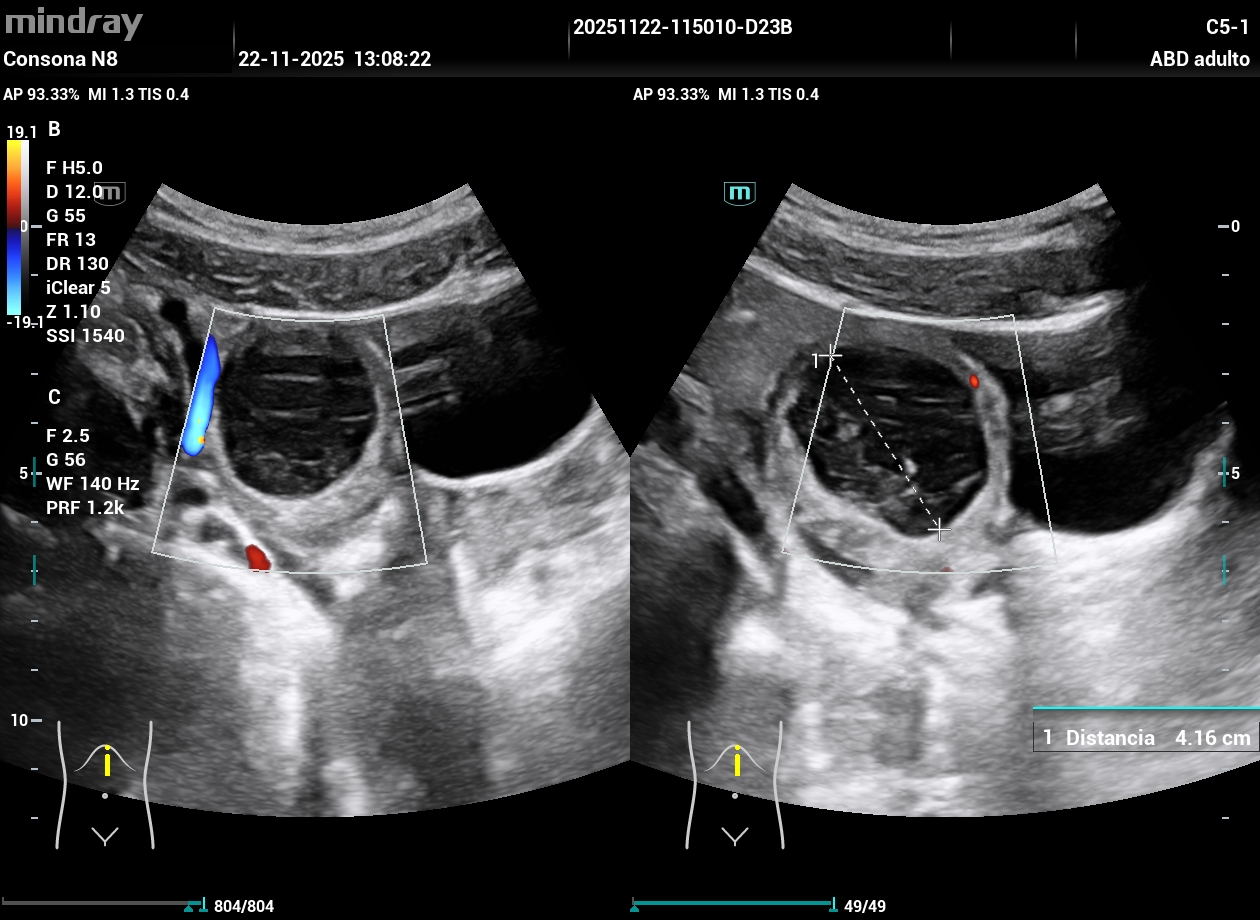

Hallazgos ecográficos

Ecografía clínica (POCUS):

Dolor lumbar irradiado secundario a masa anexial derecha compatible con quiste ovárico de gran tamaño y compresión vesical.

En Ginecología se completó el estudio, confirmándose quiste ovárico derecho, indicándose intervención quirúrgica programada.

Es importante diferenciar quistes ováricos simples sin ecos internos, como en este caso, de aquellos con ecos en su interior, característicos de quistes hemorrágicos.